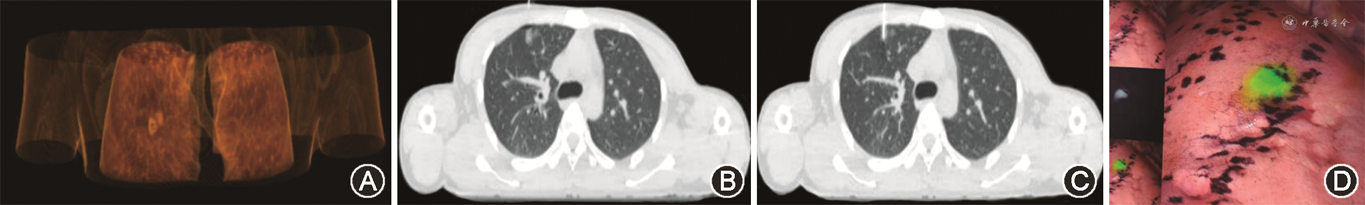

2. 定位方法:(1)术前CT引导下穿刺定位技术:患者仰卧位,采用16排CT扫描后根据磨玻璃结节位置,选择合适角度、距离以及最佳进针点(最近原则),表面消毒、铺巾,以2%利多卡因局部麻醉;再次扫描确定位置,根据吲哚菁绿使用推荐说明,缓慢注射0.05~0.15 ml吲哚菁绿;最后再次扫描确认,并观察气胸、出血等情况,嘱患者静卧休息,等待进入手术。肺结节定位时间定义为CT第一次扫描开始到最后一次扫描确认吲哚菁绿注射位置为止。(2)4 D CT联合DIBH穿刺定位技术(图1):①患者平躺采取仰卧位,双手平放两侧,联合VARIAN的4 D CT系统,在患者胸部剑突位置放置带有红外荧光点的模块,利用体表金属点判断患者呼吸运动,扫描床尾部放置红外发射器和接收红外信号的摄像机采集模块的运动装置,由专业计算机将模块运动轨迹转换为患者呼吸信号;训练患者吸气屏住,确定患者屏气范围,患者根据分屏确定前几次呼吸屏气范围,进行常规2 mm螺旋扫描;②根据CT重建图像,确定患者呼吸范围、穿刺进针点、进针深度以及倾斜角度;利用三维外置激光灯将选取进针点、进针深度以及倾斜角度在体表标记出来;③皮肤表面消毒、铺巾,以2%利多卡因局部麻醉;④取出同轴套管针,嘱患者根据显示屏内呼吸范围,吸气屏气,穿刺医师根据计划一次性进针。再次嘱患者吸气屏气,进行CT扫描病灶,确认穿刺部位统计穿刺针尖与肺结节中心三维误差,然后根据吲哚菁绿使用推荐说明书,在磨玻璃结节表面,注射浓度为0.025~2.5 mg/ml,注射量为0.05~0.15 ml(宁少勿多原则)缓慢注射吲哚菁绿;⑤术后拔掉套管针,压迫穿刺点,消毒,无菌纱布包扎;⑥进行普通CT平扫,观察是否有气胸、出血等情况,嘱患者静卧休息,等待进入手术。

试验组在X、Y两个维度上小于对照组[4.8(3,7.9)mm比7.0(3.7,12.6)mm,3.8(1.3,7.5)mm比6.6(2.9,11.2)mm](Z=-2.14、-2.34,均P<0.05),Z轴上差异无统计学意义(P=0.343)(表2)。试验组肺结节定位时间短于对照组[(9.3±3.0)min比(11.4±3.8)min;t=-3.32,P<0.001)]。

本研究中采用的4 D CT引导下联合DIBH技术进行肺结节术前定位具有如下优势:第一,定位更加精准。本研究中,试验组的吲哚菁绿注射点与肺结节三维方向的偏差在X、Y两个维度上明显小于对照组[4.8(3,7.9)mm比7.0(3.7,12.6)mm,P=0.033;3.8(1.3,7.5)mm比6.6(2.9,11.2)mm,P=0.019]。Z轴方向,由于定位CT是螺旋扫描,层厚为2 mm,所以Z轴的距离统计都为层厚的整数倍,不能测量确定的距离不具有科学性。4 D CT是专门针对胸部的一种实用性工具,它能实时检测与呼吸运动相关的胸腔内器官的运动范围[18]。DIBH是一种在放疗技术上运用比较多的一种技术,大量文献报道[19, 20]DIBH在运动管理上是一种优秀技术,尤其精准定位,但是呼吸量一致性和呼吸潮量多少很难把握。4 D CT引导下联合DIBH技术是通过胸廓的起伏,实时检测呼吸运动。理论上4 D CT可使患者的每次呼吸幅度尽量保持一致,从而更加精准地定位肺结节,尤其是位于肺裂、肺下叶等活动度较大的位置的肺结节[21],进而做到肺结节精准切除,在保证足够切缘的同时保留更多的肺功能。第二,定位时间缩短。数据显示试验组肺结节定位时间明显短于对照组[(9.3±3.0)min比(11.4±3.8)min,P<0.05]。对照组肺结节定位时间长可能与4 D CT引导下联合DIBH技术可以减少因肺活动较大而反复更换胸壁表面穿刺定位点的频率有关。而试验组患者实施定位时,由于患者训练呼吸量和潮气量一致,在单次屏气就可达到预期效果,减少CT扫描次数。第三,适用范围广。位于特殊位置(如肩胛骨或者乳腺受挡部位、近膈肌或心脏大血管位置等)的肺结节,通过4 D监视下选取适应屏气范围,避开肋骨、脊椎等障碍物的进针角度也可以达到精准定位肺结节。